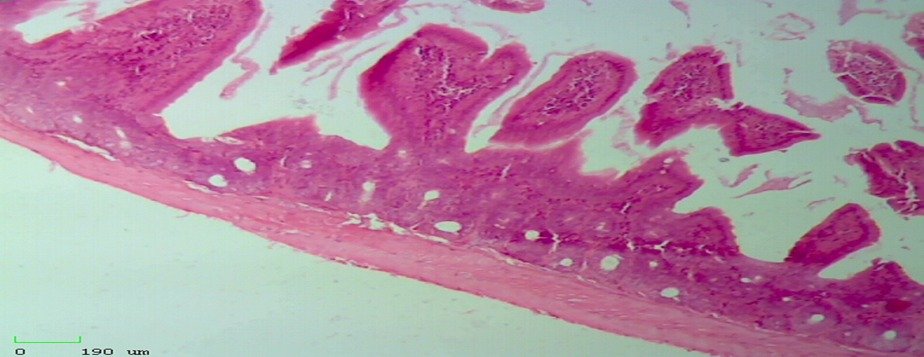

• Health Effects of Diets (High-Fiber Diet and Intermittent Fasting) on Experimental Animals

Ghenaa Hamid Abdulkreem, Feryal Farouk Al-Azzawi, Noor Jumhaa Fadhil

18-31

Abstract viewed: 102 PDF downloaded: 115

DOI : 10.55529/ijaap.36.18.31

• PDF